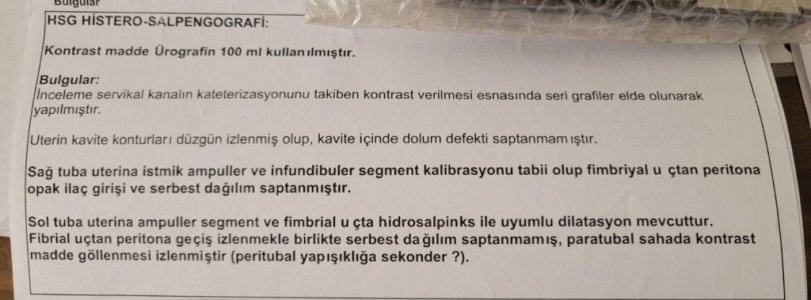

Ayrıca Rahim filmi raporunu yorumlayabilir misiniz? Doktorun dediği gibi sol tüpteki sıvı rahime gelerek tüp bebek için konulan embriyonun tutunmasını engeller mi?

Rahim Filmi raporu özel bir hastaneye ait.

Ayrıca Rahim filmi raporunu yorumlayabilir misiniz? Doktorun dediği gibi sol tüpteki sıvı rahime gelerek tüp bebek için konulan embriyonun tutunmasını engeller mi?

Rahim Filmi raporu özel bir hastaneye ait.